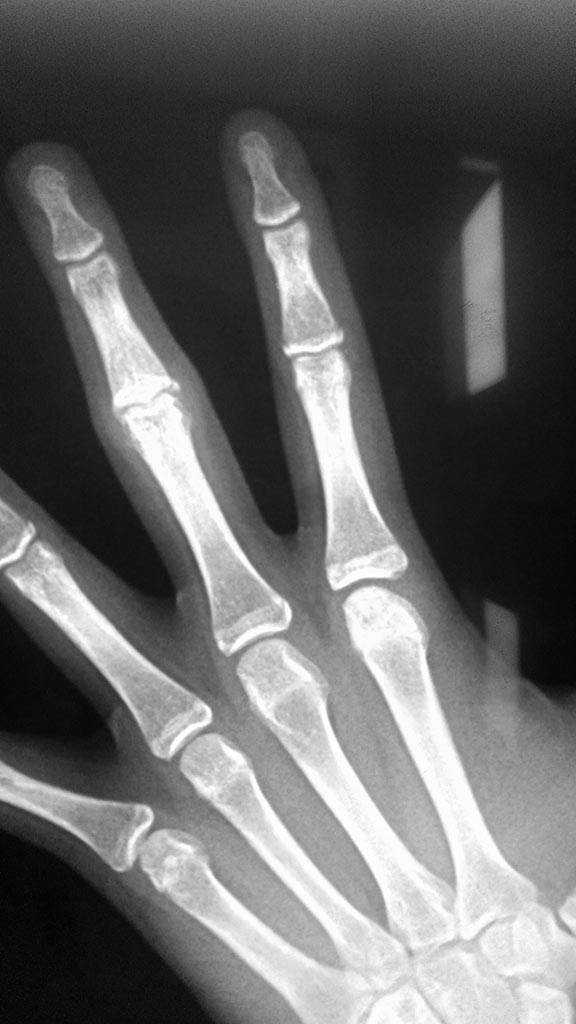

Девочка 14 лет. В июле 2016 года ударила палец о мяч. Лечились гипсовой иммобилизацией 4 недели и всё. Обратились через 5 месяцев, с жалобами на сохранившееся ограничение сгибания.

При осмотре: сгибание в проксимальном межфаланговом суставе 3 пальца кисти на 90 градусов.

На рентгенограммах: фрагментарный перелом волярой части эпифиза со смещением на первичных снимках, сохранившееся (усилившееся) через 5 месяцев. Состояние подвывиха.

прямая проекция